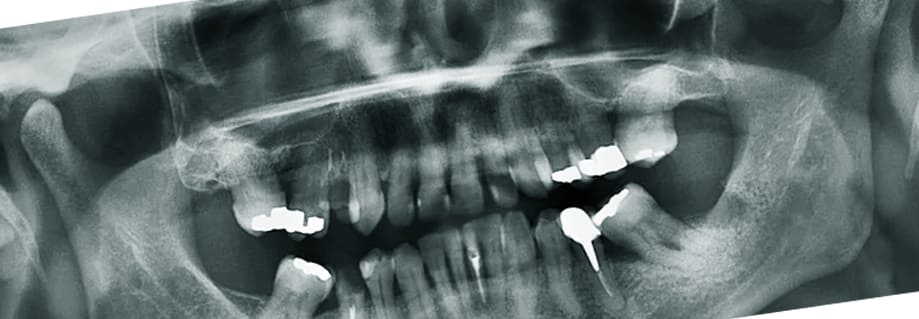

어떤 분들은 치아가 빠지면 그대로 방치하는 분들이 있습니다. 장기적인 관점에서 잇몸이 상할 수 있고 빈 공간에 음식물 찌꺼기가 계속 쌓일 수 있기 때문에 잇몸 건강을 생각하면 굉장히 좋지 않습니다. 또한 음식들에 물리적인 충격으로 치주염이 걸릴 수 있는데요. 더 나아가 음식물을 제대로 씹지 못해 소화불량, 위장질환 등이 걸릴 확률이 높아지며 빠진 공간에 공기가 세어나가 발음이 어눌해 질 수 있습니다.

그렇기 때문에 임플란트를 통해 빠진 치아를 대체해야 합니다. 특히 나이가 들면 이빨, 잇몸도 노화가 되어 차이 밑 혈관이나 신경들이 약해치는데 이런 부분도 고려해야 합니다.

최근에는 3차원 CT스캔을 이용해 자신의 치아 상태에 최적화된 임플란트를 만들 수 있을정도로 꼼꼼한 진단과 세심할 시술이 가능하니 적응할 수 있을까 라는 걱정은 하지 않아도 됩니다.